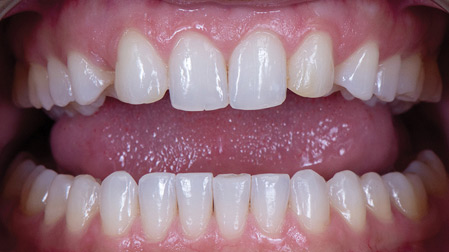

An Alternative Prosthetic Design for Lower Full-Arch Implant Restorations

Frontal view of finished prosthesis.

Replacing a full set of teeth with dental implants, especially in the mandible, has been well researched and is often a life-changing treatment for many patients. This treatment involves the extraction of failing teeth, immediate implant placement, immediate loading of the implants with a fixed provisional prosthesis, followed by the fabrication of a definitive prosthesis … Read more